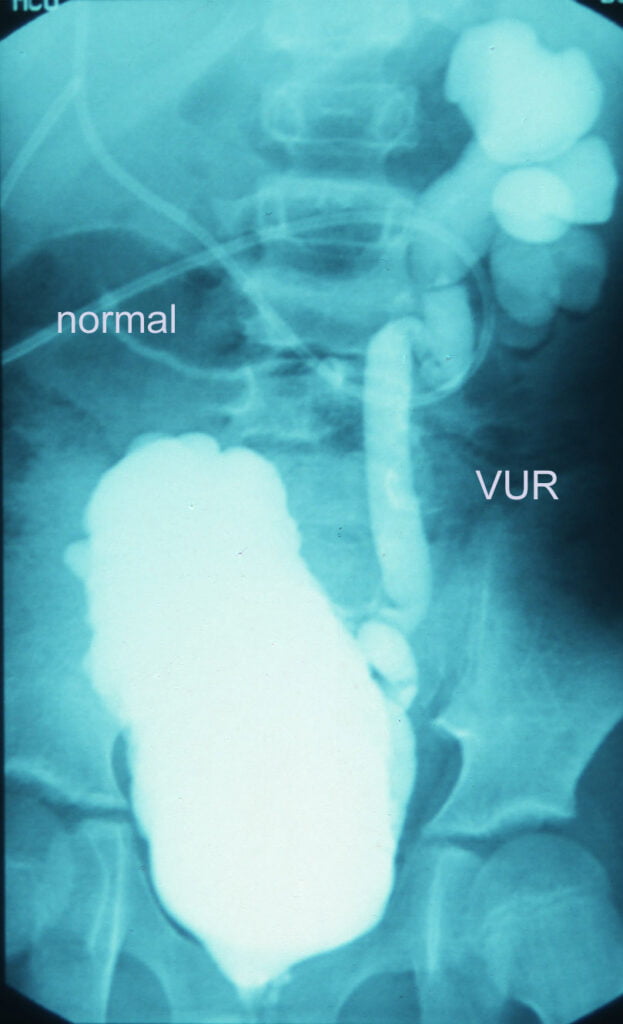

How do we diagnose VUR?

A test called MCU is done to diagnose VUR. In this a special radio opaque dye is injected via a catheter into the bladder. X-rays are taken while the child passes urine. Normally urine should not go up towards kidneys. But in children with VUR it goes up.